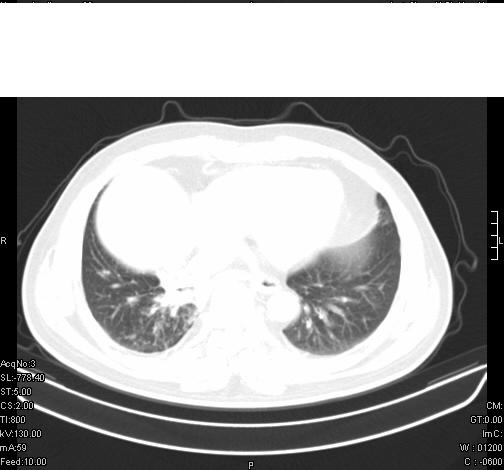

前几天,发了患者的平扫片,患者抗炎一周后增强扫描。右中叶病灶吸收明显,但下叶病灶未见明显吸收。右肺门可见结节影,看来凶多吉少

右肺下叶散在的斑片状致密影,下叶支气管变窄。考虑:右肺慢性炎症。

支持:右肺下叶散在的斑片状致密影,下叶支气管变窄。考虑:右肺慢性炎症。

病灶在下叶,散发,抗炎治疗有效,考虑炎症,楼主说的肺门结节看的不明显